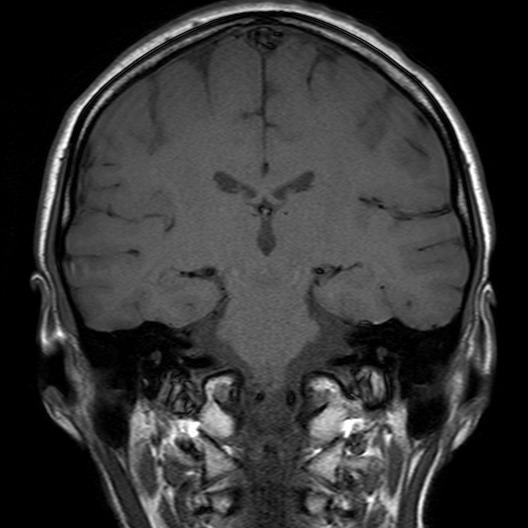

Figure 4: Samples from the non-tumorous class across different imaging planes. The top row shows healthy brain scans without visible abnormalities, and the bottom row shows examples of non-tumorous lesions (e.g., cysts or abscesses).

Non-tumorous: This control class includes both healthy brain scans without visible abnormalities and scans with non-neoplastic, space-occupying lesions (e.g., cysts, abscesses, or vascular malformations). Incorporating such cases improves the dataset’s robustness for both binary (tumorous vs. non-tumorous) and multi-class classification tasks. Figure 4 presents representative examples of healthy and non-tumorous lesion cases across different imaging planes.